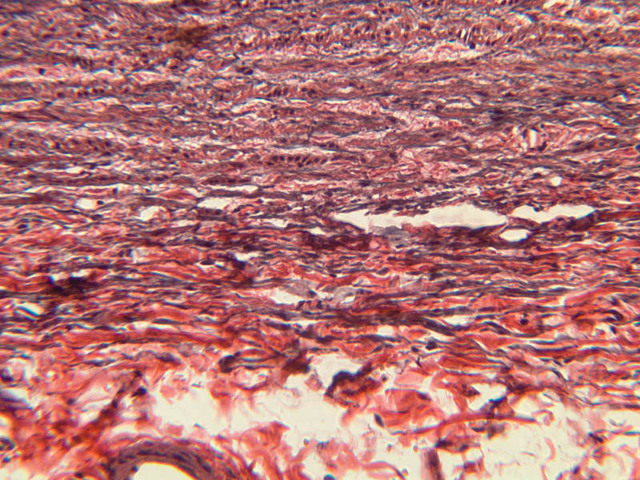

The blood is pumped from the heart into large, elastic (conduction) arteries. Examine a section of the aorta (A-26, H&E [2.5x, 10x, 20x, 40x-labeled] [2.5x, 10x-labeled, 20x, 40x]) which is a typical elastic artery. Although the tunica intima and tunica media are difficult to distinguish, note that together they are much thicker than the tunica adventitia. Using high power magnification, examine the tunica media and identify the cell types and fibers, recalling that elastic tissue appears light pink and refractive in H&E preparations. Compare this slide with a section of aorta stained to demonstrate elastic fibers (A-27, verhoeff [2.5x, 10x, 20x, 40x-labeled] [2.5x, 10x]).

Note how extensive the elastic tissue is in the tunica media. The elastic tissue is arranged in the form of numerous concentric elastic lamellae, which are cross connected by slender elastic fibers. Observe the distribution of elastic fibers in the tunica intima (A- 27 [2.5x, 10x, 20x, 40x]) and tunica adventitia (A-27 [10x, 20x, 40x]). The internal and external elastic membranes are not well demarcated in the aorta since so many elastic lamellae are present. The elasticity of the aorta allows it to expand and absorb much of the pressure during contraction of the left ventricle (i.e., systole). When the ventricle relaxes (diastole), the elastic aorta contracts, continuing the movement of blood into the medium and muscular arteries.